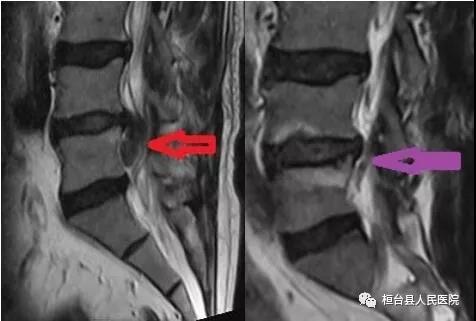

术前巨大髓核下垂,术后脱垂的髓核消失

术前:黑色区域是髓核,术后:黑色区域髓核消失